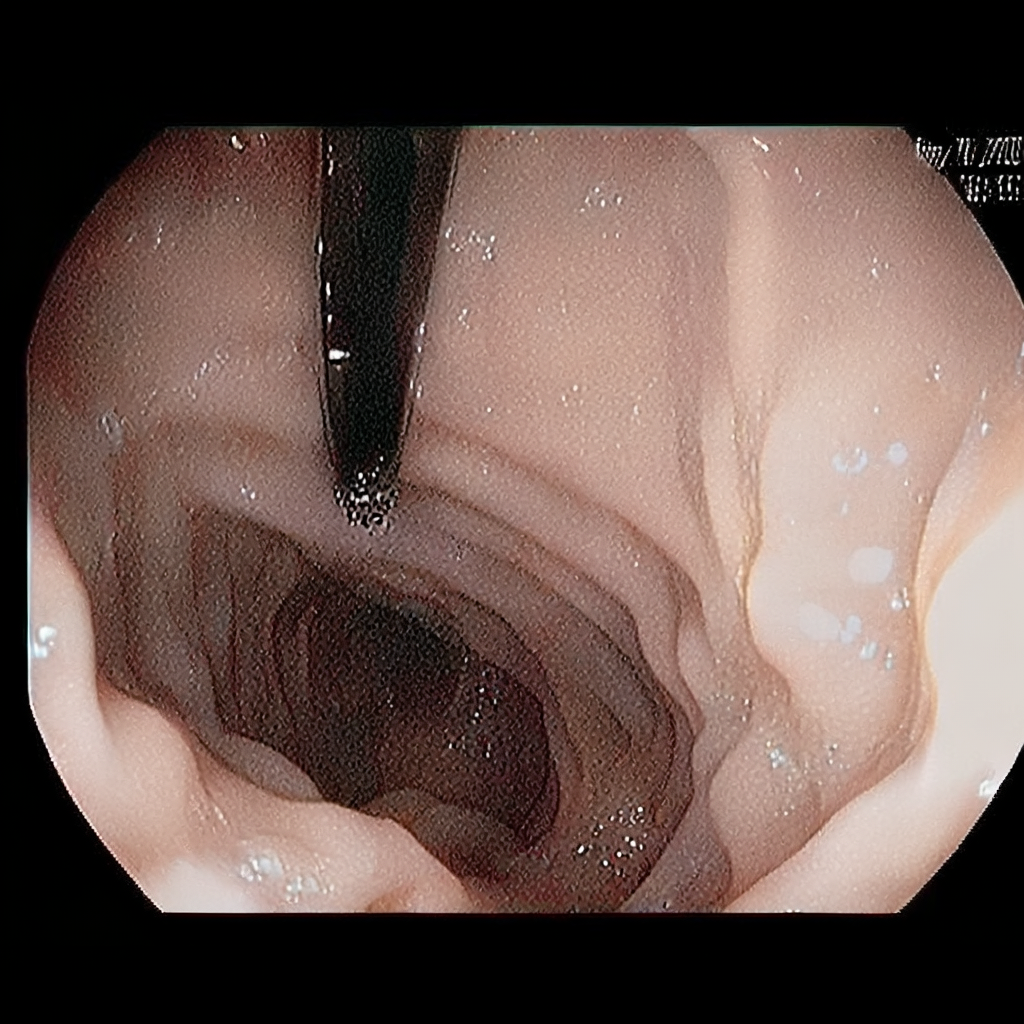

Diffusion models have recently gained significant traction due to their ability to generate high-fidelity and diverse images and videos conditioned on text prompts. In medicine, this application promises to address the critical challenge of data scarcity, a consequence of barriers in data sharing, stringent patient privacy regulations, and disparities in patient population and demographics. By generating realistic and varying medical 2D and 3D images, these models offer a rich, privacy-respecting resource for algorithmic training and research. To this end, we introduce MediSyn, a pair of instruction-tuned text-guided latent diffusion models with the ability to generate high-fidelity and diverse medical 2D and 3D images across specialties and modalities. Through established metrics, we show significant improvement in broad medical image and video synthesis guided by text prompts.

In this work, we focus on the ability of LDMs to generate novel datasets to overcome class imbalances traditionally associated with medical data, and potentially reduce the need for manual annotation of medical 2D and 3D data. We present MediSyn, a pair of text-guided latent diffusion models for broad medical 2D and 3D modality synthesis. To overcome the scarcity of labelled medical data, we leverage a vast corpus of more than 5 million image-caption pairs and 100,000 video-caption pairs collected from the public domain across numerous medical specialties, and integrate comprehensive natural language annotations to develop a pair of versatile diffusion models for the medical domain.

We assembled a set of 5,785,333 medical image-caption pairs, covering 8 specialties and 9 imaging modalities, to train Medisyn’s 2D model. We reserved an additional 1000 image-caption pairs (125 pairs from each specialty) for model evaluation.

| Gastroenterology | 7,568 |

Our findings demonstrate Medisyn’s remarkable ability to generate high-fidelity and diverse medical images, image sequences and volumetric scans across various medical subspecialties and imaging modalities. Other medical text-driven diffusion models, such as TauPETGen [42] for tau PET images and GenerateCT [43] for chest CT volumes, have proven successful in generating high-quality images that accurately depict anatomical features and clinical conditions. However, these models are constrained to a single imaging modality and anatomical region, thereby restricting their applicability. Moreover, they were trained on relatively small datasets sourced from a limited number of institutions, which could lead to more biased outputs. In contrast, Medisyn, having been trained on one of the largest publicly accessible medical image and video datasets to date, is equipped to synthesize data that cover numerous medical disciplines, population groups, and disease states. Leveraging our two models, we can synthesize new medical datasets as well as augment existing ones, potentially improving a wide array of medical machine learning tools, both general and specialized. Additionally, our models can minimize the need to repeatedly fine-tune on specific datasets for generating different imaging modalities, thus reducing computational costs for academic labs.

In summary, we introduced a pair of text-conditional LDMs trained on an extensive medical image and video dataset covering various medical subspecialties and imaging modalities. By generating high-fidelity and diverse medical 2D and 3D images, Medisyn illustrates the potential for a singular framework to broadly address the challenge of data scarcity in healthcare.